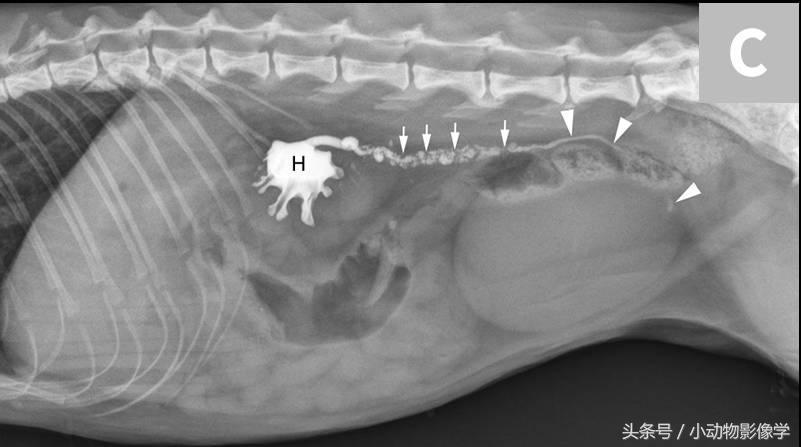

图7C、同一只猫的顺行性超声引导肾盂造影影像,可见中度肾积水(H)和输尿管内多处充盈缺损(结石)(箭头)。尽管输尿管结石数量很多,但动物输尿管仍只是部分梗阻,因为阳性造影剂在结石远端(三角箭头)。